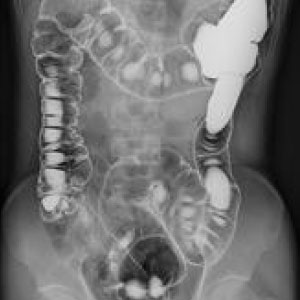

エックス線を利用して検査をするいわゆる“レントゲン撮影”です。

胸部、腹部、全身の骨の撮影を行います。心臓の大きさや肺の異常陰影、ガスの状態や骨の形、骨折の有無、関節の状態などがわかります。

当院ではフラットパネル(FPD)というシステムを導入し従来よりもエックス線の感度が高く低被ばくで撮影ができるようになりました。撮影効率も向上し撮影待ち時間も短縮しています。

エックス線を利用して体内をリアルタイムに見ながら検査を行います。胃のバリウム検査や腸のバリウム検査、骨折、脱臼の整復術や神経根、脊髄腔造影、嚥下造影(VF)など多岐にわたり検査を行っております。